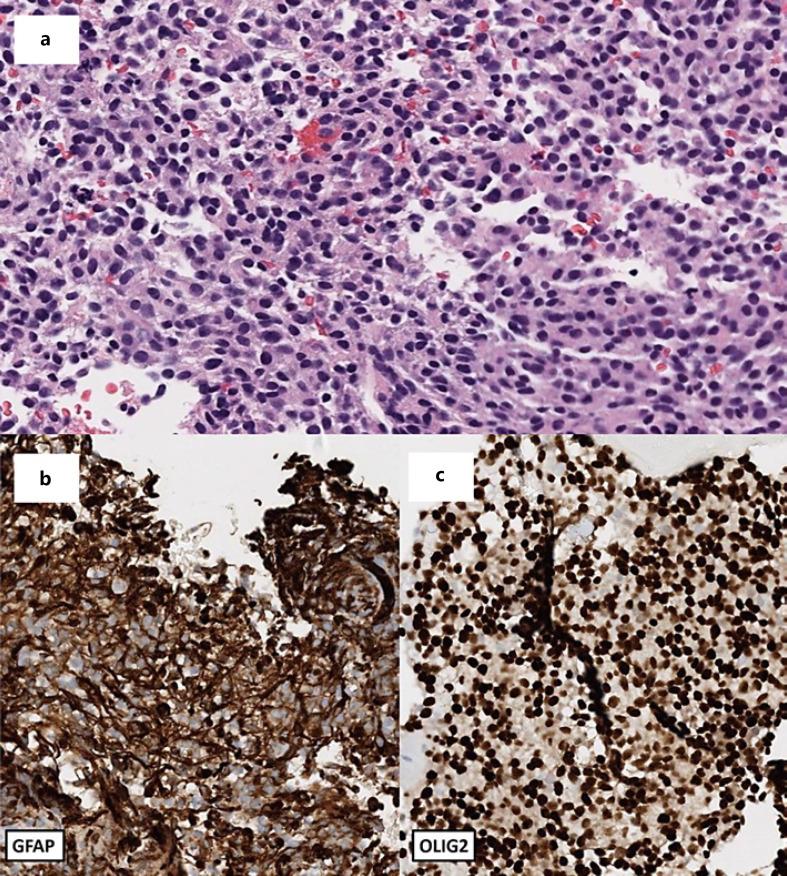

Recent advancements in understanding the biology of glioblastomas (GBM) and increasing adoption of genomic sequencing in oncology practice have led to the discovery of several targetable mutations in these cancers. Among them, the BRAF V600E mutation can be found in approximately 3% of GBM. Despite the aggressive nature of GBM, metastatic disease is rarely observed. While there are growing data utilizing BRAF-targeting strategies in patients with GBM, data examining their efficacy in cases of metastatic GBM are lacking. We present the case of a 46-year-old female with GBM, isocitrate dehydrogenase (IDH)-wildtype and O-methylguanine-DNA methyltransferase promoter (MGMT) unmethylated, BRAF V600E-mutant, and MYC amplified with extra-central nervous system spread to the spine and lung. Four months after completion of treatment with standard chemoradiation and temozolomide, the patient developed severe back pain, leading to the eventual discovery of her metastatic disease. Based on the presence of the BRAF V600E mutation, the patient was treated with and achieved an intracranial and systemic response to combination BRAF-MEK targeted inhibition for 9 months before evidence of progression.

近年来,在胶质母细胞瘤(GBM)生物学认识方面的进展以及肿瘤学实践中基因组测序应用的增加,促使人们在这些癌症中发现了几种可靶向的突变。其中,BRAF V600E突变在约3%的GBM中可见。尽管GBM具有侵袭性,但很少观察到转移性疾病。虽然有越来越多的数据表明在GBM患者中使用BRAF靶向策略,但缺乏关于其在转移性GBM病例中疗效的数据。我们报告了一例46岁女性GBM患者,异柠檬酸脱氢酶(IDH)野生型、O-甲基鸟嘌呤-DNA甲基转移酶启动子(MGMT)未甲基化、BRAF V600E突变且MYC扩增,伴有中枢神经系统外扩散至脊柱和肺部。在完成标准放化疗和替莫唑胺治疗四个月后,患者出现严重背痛,最终发现其转移性疾病。基于BRAF V600E突变的存在,患者接受了BRAF-MEK联合靶向抑制治疗,在出现疾病进展迹象之前,颅内和全身反应达9个月。